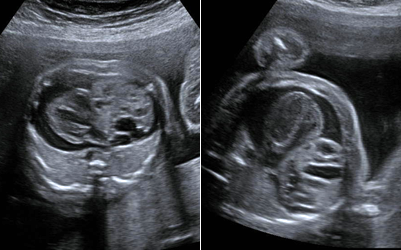

Cardiac teratoma and pericardial effusion.

- Fetal brain and spine anomalies including Spina Bifida, Fetal Ventriculomegaly, Dandy-Walker Malformation, and Agenesis of the Corpus Callosum.

Dandy Walker Malformation.